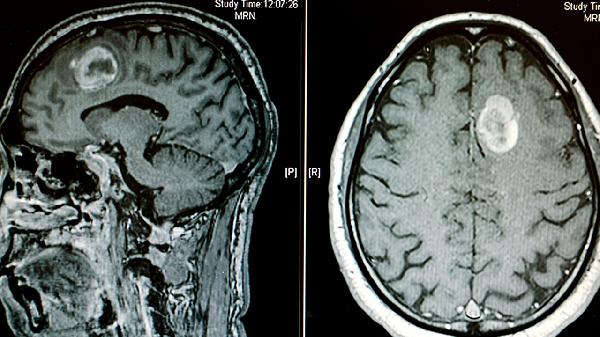

适用于脑外伤或手术后恢复期的认知康复,能减轻脑缺氧导致的思维混乱。但脑梗死急性期、癫痫发作期禁用,用药期间需要定期监测肝肾功能,儿童用量须严格遵医嘱调整。